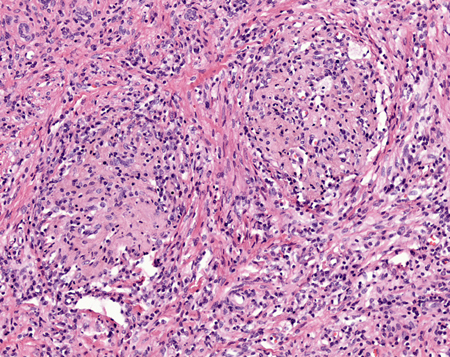

[Figure caption and citation for the preceding image starts]: Coloração H&E: visualização de alta potência dos granulomas encontrados na pielonefrite xantogranulomatosaCortesia do Dr. Jean L. Olson, MD, Departamento de Patologia, Universidade da Califórnia, San Francisco, EUA [Citation ends].

[Figure caption and citation for the preceding image starts]: Visualização de potência muito alta das células xantomatosas, que são macrófagos preenchidos de lipídiosCortesia do Dr. Jean L. Olson, MD, Departamento de Patologia, Universidade da Califórnia, San Francisco, EUA [Citation ends].